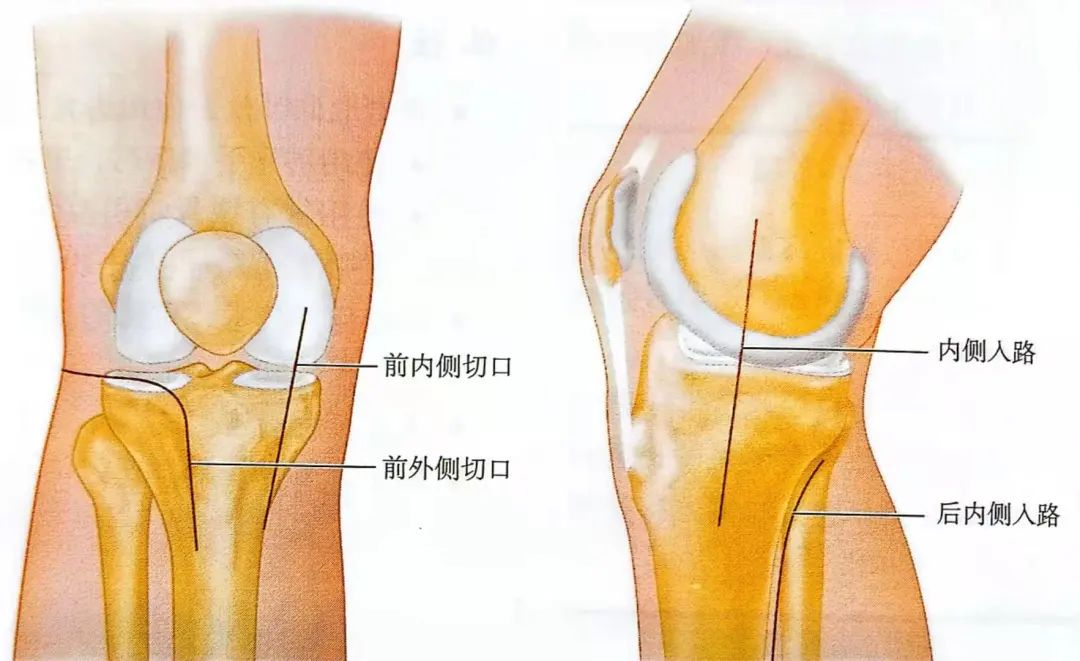

通常采用小切口复位关节面。切口要根据骨折情况来选择,通常包括:①前外侧或者前内侧切口;②内侧或后内侧切口。

▲示意图

操作安全范围参见上文。